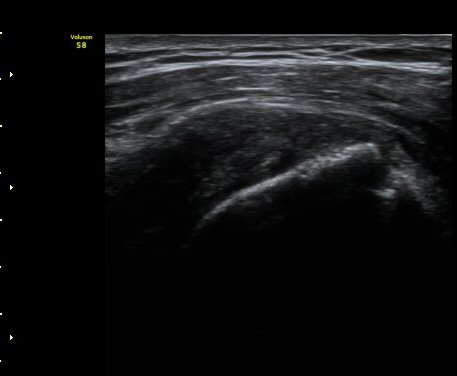

ÃÊÀ½ÆÄ °Ë»ç

2049205267_d18eca99_IMG_20140331_2_1-c.jpg